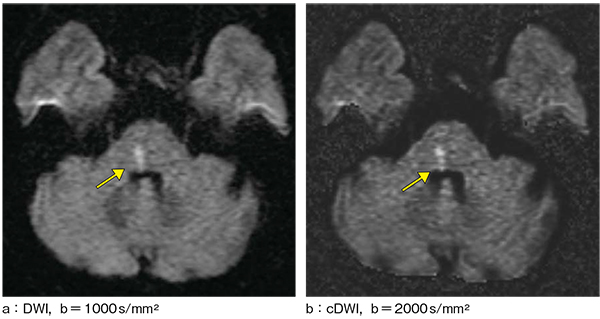

1.脳梗塞

症例は60歳代,女性。脳幹部は近傍の空気の影響もあり,ルーチンで撮像しているb=1000s/mm2のDWI(図2 a)では病変が少しわかりにくい。b=2000s/mm2のcDWI(図2 b)では背景の信号が抑制されたため,梗塞部が明瞭になっている。

図2 脳梗塞症例